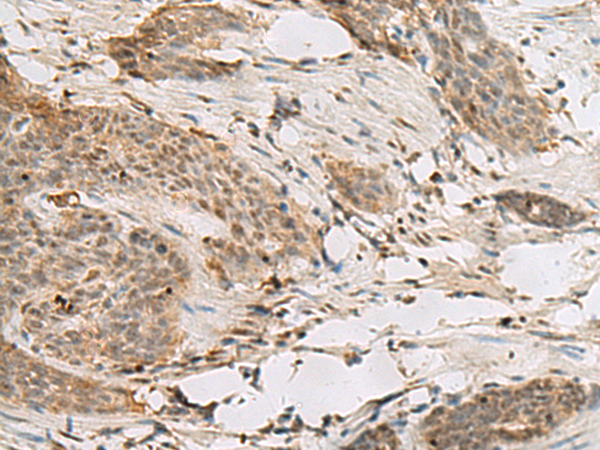

分类: 科研抗体货号: P13578别名: SS1; DRB1; HLA-DRB; HLA-DR1B应用: IHC反应种属: Human